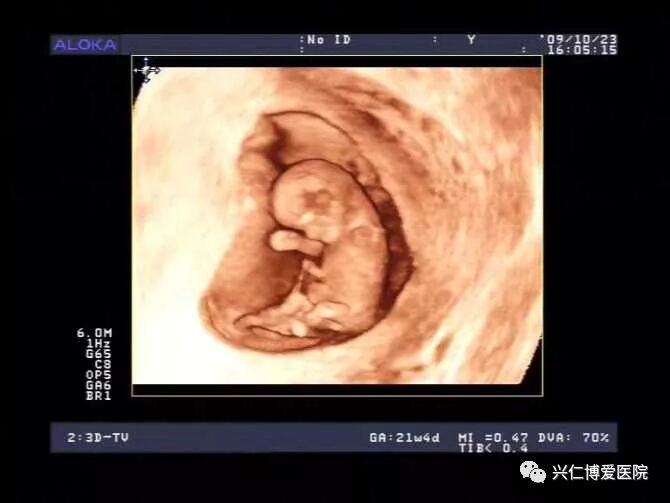

随着科技的发展,B超已不能满足人们的需求了,于是有了四维彩超。四维彩超的全称为四维彩色超声诊断仪,是目前世界上最先进的彩色超声设备。四维彩超能够表面成像,若胎儿有唇腭裂、四肢发育畸形、脑膜膨出、脊柱裂、腹壁裂等先天畸形,都能更清晰地查出来,也有利于医生做出判断。

正因为四维彩超的成像清晰,能清楚得看到胎宝宝的样子,所以,很多准妈妈都想给宝宝去做个胎儿写真集,即去做四维彩超检查。但是四维彩超检查可不只有这点作用哦,本文小编就带你来了解下四维彩超的作用!